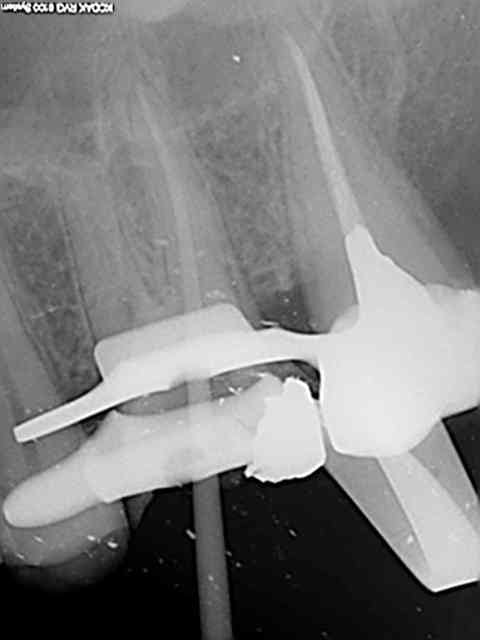

26, 60 mn endo molaire dont 30 pour trouver le canal DV (chambre calcifiée). J'ai failli jeter l'éponge mais le sx a fini par s'engager. Grosse frayeur toutefois avec le s1 sur endomaster car il a bipé d'ès son entrée dans le canal, mais c'était du à un excès d'irrigant. Ouf !